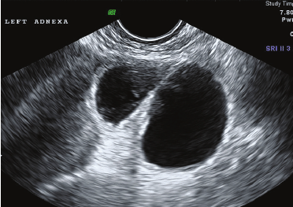

- Ultrasound – follicular monitoring